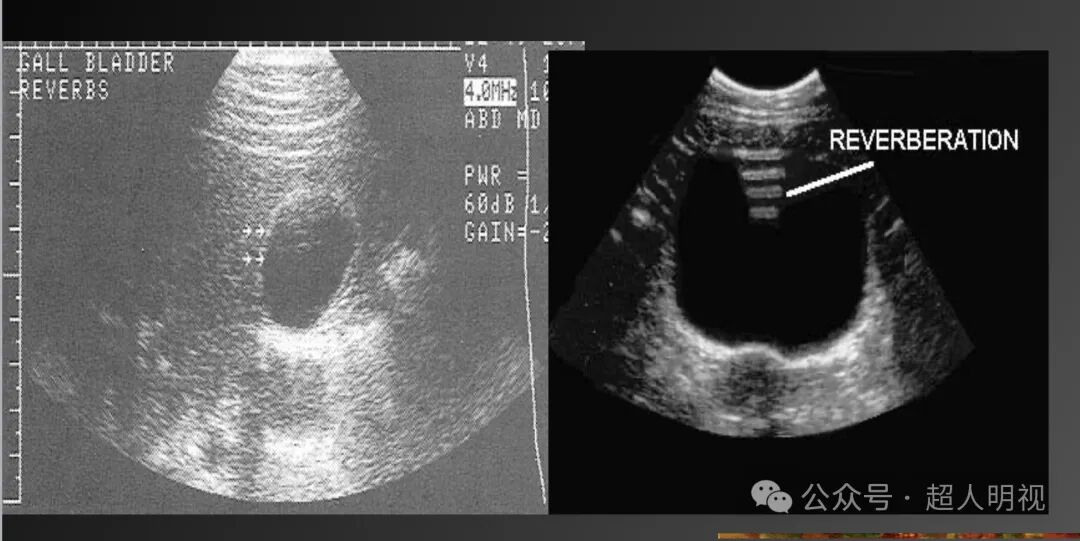

- 混响伪像(声波在探头与强反射体间多次反射,间隔均匀且逐渐减弱)

彩超伪像是什么超声伪像_https://www.jmylbn.com_新闻资讯_第6张

- 彗星尾伪像(金属等强反射体导致密集短小回声线)

彩超伪像是什么超声伪像_https://www.jmylbn.com_新闻资讯_第7张